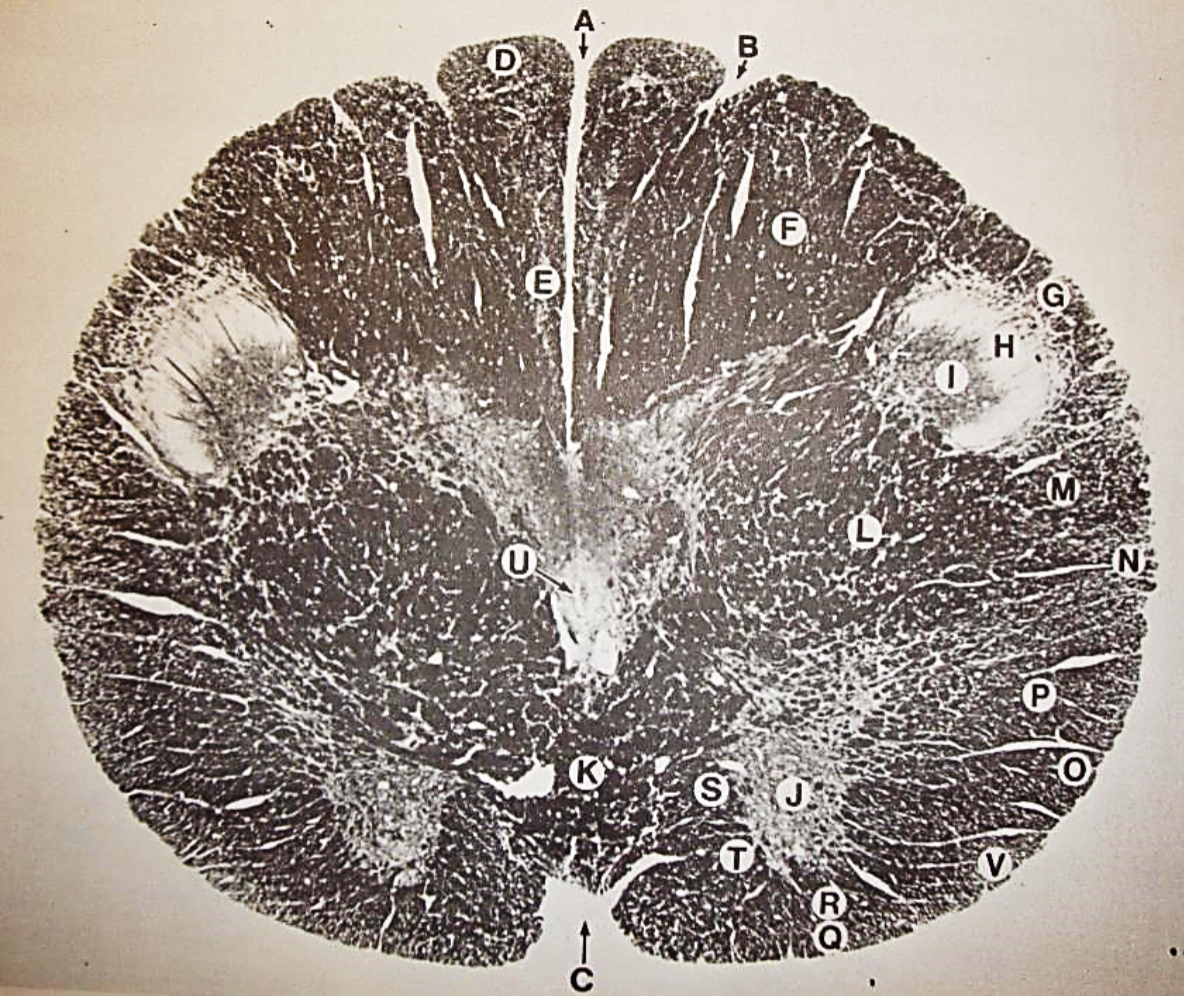

A

posterior median sulcus

B

posterior intermediate sulcus

C

anterior median fissure

D

gracile fasciculus

E

Gracile nucleus

F

fasciculus cuneatus

G

spinal trigeminal tract

H+I collectively

spinal trigeminal nucleus

J

Accessory nucleus

K

pyramidal decussation

L

lateral corticospinal tract

M

rubrospinal tract

N

posterior spinocerebellar tract

O

anterior spinocerebellar tract

P

lateral spinothalamic tract

Q

anterior spinothalamic tract

R

lateral vestibulospinal tract

S

medial longitudinal fasciculus

T

tectospinal tract

U

central canal